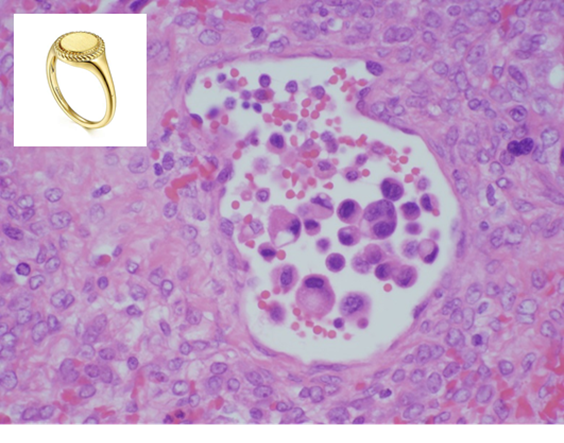

2) can also be Krukenberg’s tumor where gastric carcinoma metastasizes to ovaries bilaterally

→ these are mucin producing and forms signet ring cells on histopathology